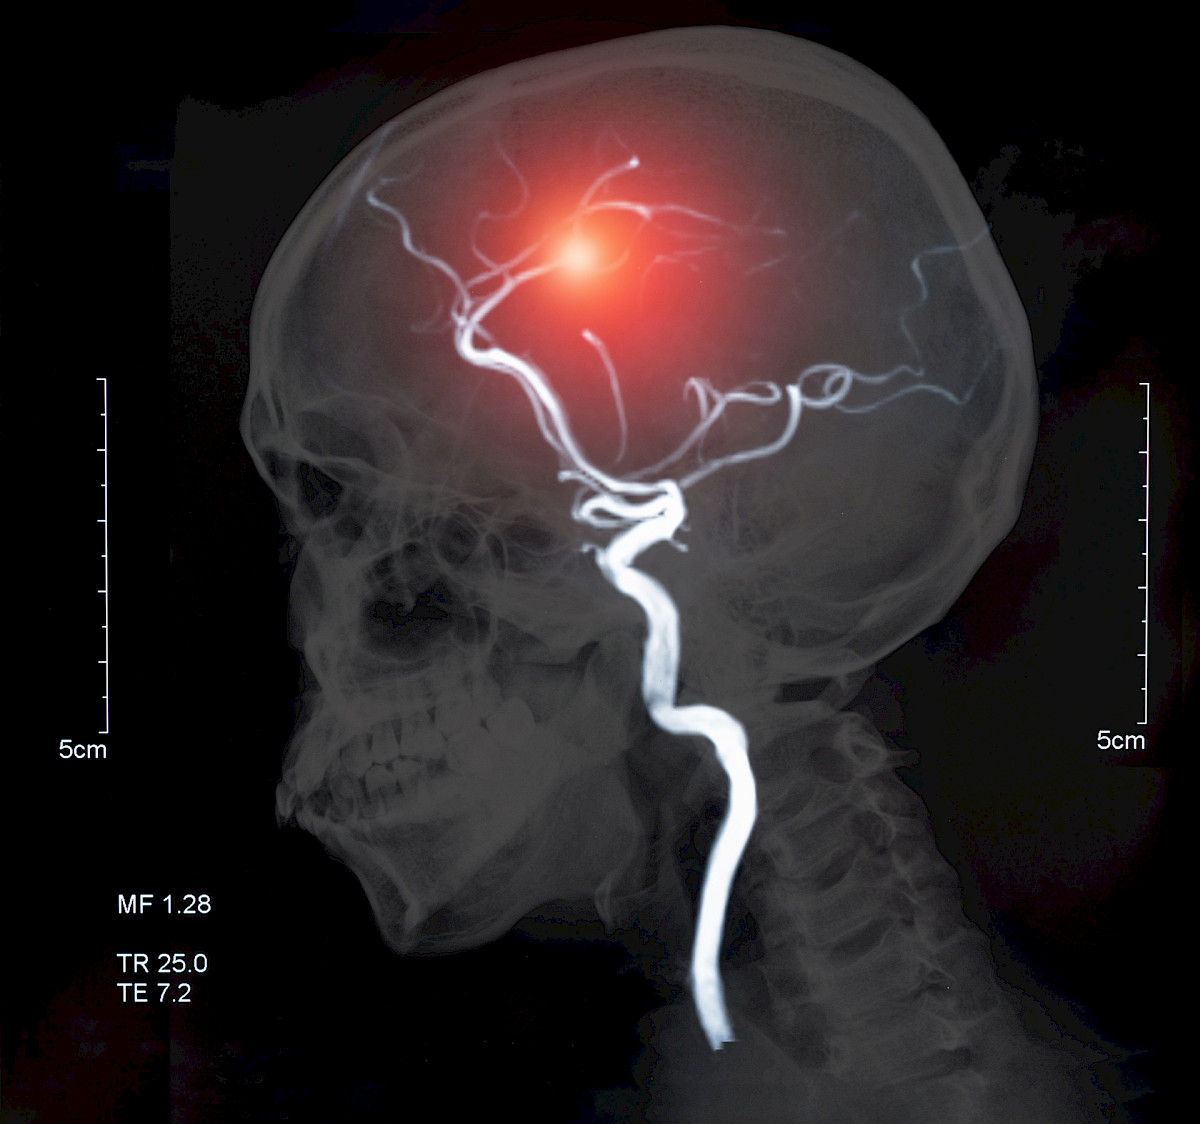

Suun bakteerit voivat vaikuttaa aivovaltimoaneurysman syntyyn

Suun bakteerit saattavat verenkiertoon päästessään vaikuttaa aivovaltimopullistumien eli -aneurysmien syntyyn ja puhkeamisalttiuteen useiden tulehdusmekanismien kautta, selviää tuoreesta Neurosurgial Review -lehdessä julkaistusta katsauksesta. (Hallikainen J ym. Neurosurg Rev. 7.2.2020)

Noin kolmella prosentilla aikuisista on aivovaltimopullistuma, joka puhjetessaan voi aiheuttaa hengenvaarallisen lukinkalvonalaisen verenvuodon. Kaikki eivät puhkea, mutta elämänmittaisessa suomalaisessa seurantatutkimuksessa on havaittu, että noin joka kolmas vuotamattomina löytyneistä aivovaltimoaneurysmista lopulta puhkesi. Tupakointi, korkea verenpaine ja alkoholin liikakäyttö lisäävät aneurysmariskiä, mutta monilla potilailla ei ollut mitään tunnettuja riskitekijöitä.

Itä-Suomen yliopiston ja Kuopion yliopistollisen sairaalan tutkijat osoittivat hiljattain, että laajalle levinnyt ientulehdus liittyy aivovaltimoaneurysmien muodostumiseen ja lukinkalvonalaisen verenvuodon riskiin. Tampereen yliopiston ja ylipistollisen sairaalan tutkijat osoittivat aiemmin, että puhjenneiden ja puhkeamattomien aivovaltimoaneurymien seinämistä löytyi suuperäisten bakteerien DNA:ta. Suun sairauksilla on havaittu vastaavia yhteyksiä myös vatsa-aortan aneurysmiin.